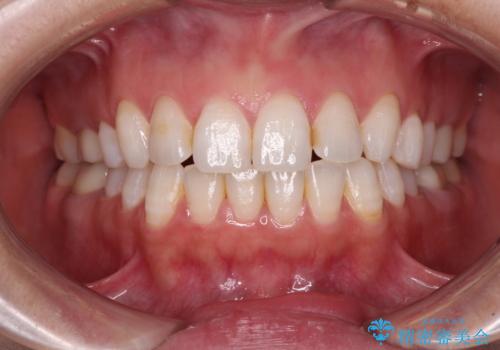

- 奥歯の銀歯が外れたことをきっかけに、全ての銀歯をセラミックに替えたいとのことで来院された患者様です。

第一大臼歯4本と、メタルインレーが装着されている2歯をセラミッククラウンならびにセラミックインレーにて補綴治療・修復治療を行うこととしました。

口腔内から、土台も含め銀歯がなくなったことでメタルフリーとなりました。